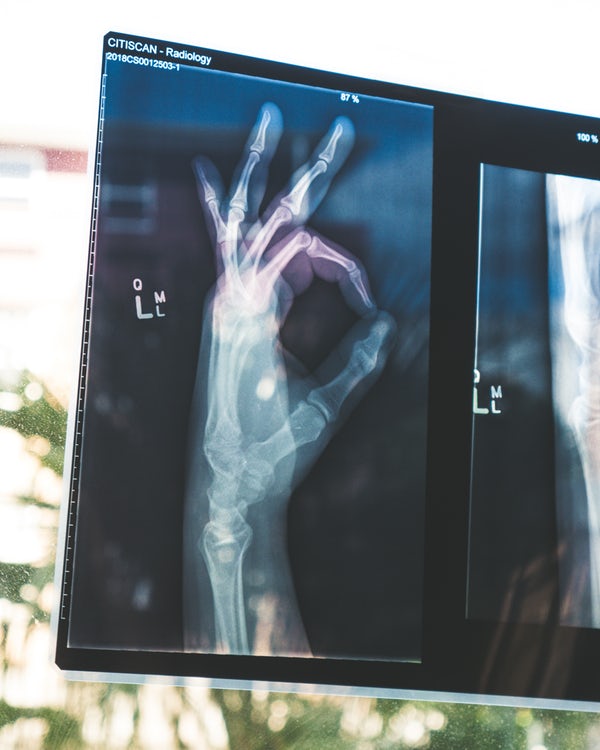

It is often called the ‘’silent disease’’ as it usually has no signs or symptoms until a fracture occurs. These fractures  can occur from a minor injury or fall and are called ‘’minimal trauma fractures’’. The most common fracture sites are the spine, hip and wrist.  It is not just a Women’s disease as 1 in 3 women and 1 in 5 men will have an osteoporotic fracture in their lifetime.  Osteoporotic fractures can be devastating leading to disability, loss of independence, depression and chronic pain. This is especially the case for hip fractures with 50% of elderly people needing long term nursing care and up to 15% dying within 4 months of the fracture.  The cost of osteoporotic fractures is greater than that of heart attacks, stroke and breast cancer.

If you have strong risk factors for osteoporosis, are over the age of 70 or have had a minimal trauma fracture, your doctor may order a Bone Density Scan (DEXA scan). This scan is like an X-ray which measures the thickness of the bones in the spine and hip. The test gives a result call a T-score which compares your bone density to that of young healthy adults. If your T-score is -2.5 or lower, this indicates you have Osteoporosis and your fracture risk is high. If it is between -1 to -2.5, this indicates ‘’osteopenia’ which means you have mild thinning of the bone and are at risk of developing osteoporosis. Normal bone density is greater than -1. Your doctor will use your T-score to help decide your management plan.  These scans may be repeated every 2 years depending on your risk level.